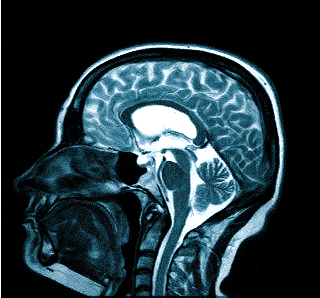

МРТ при головных болях (в трех проекциях): специальная программа выстраивает объемные изображения полученных срезов, что позволяет увидеть даже мельчайшие изменения и отдифференцировать патологию от нормы

Причин головной боли множество, и их не всегда возможно определить без помощи современных способов визуализации. Цефалгию вызывают: повышенное внутричерепное давление, сосудистые мальформации, опухолевые процессы, постравматические осложнения. Какую МРТ делать при головной боли или предпочтительней пройти КТ — зависит от предполагаемого характера патологии. Все методы являются взаимодополняющими, но что лучше в конкретном случае, выбирает врач с учетом жалоб, показаний и противопоказаний. МРТ и КТ с контрастным усилением позволяют получить сопоставимые по качеству снимки, но при этом используют разные принципы построения изображений. Чем раньше будет найдена причина и проведено адекватное лечение, тем больше шансов на полное выздоровление.